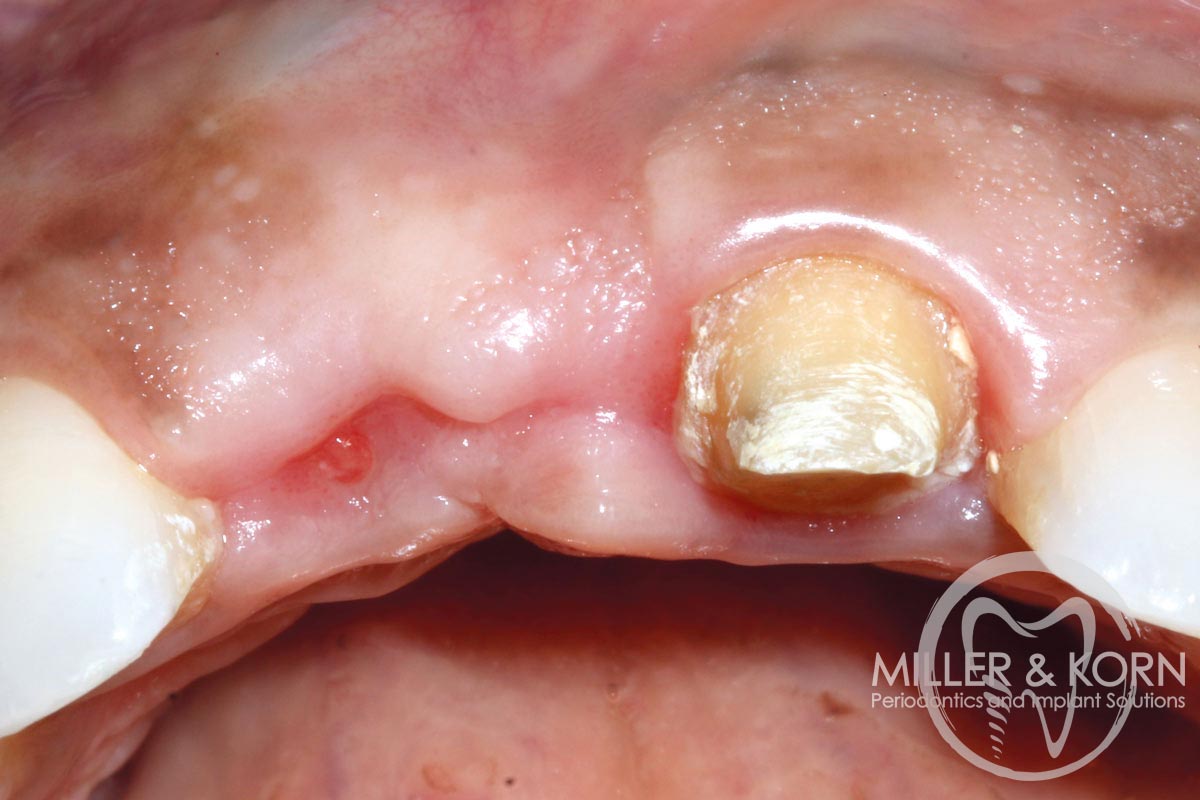

18/22 - Placement of healing abutment. Note buccal convexityImmediate implant placement and regeneration of ridge using an allograft bone ring and Jason® membrane - Drs. Miller and Korn